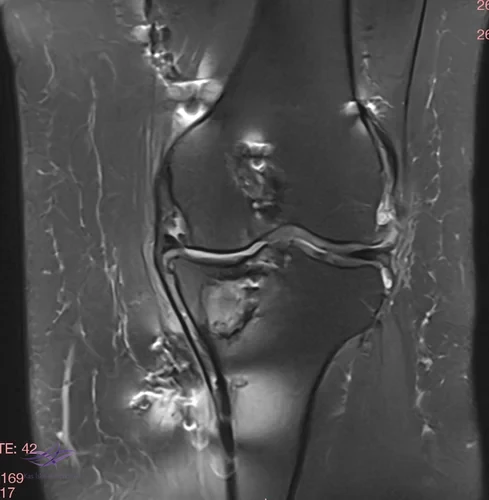

İncelemeler: USG'de minimal suprapatellar efüzyon. MCL heterojen görününde fibrillar yapı bozulmuş. Direkt grafi ve MRG'leri ektedir.

Resim 2. Resim 2. Koronal MRG.